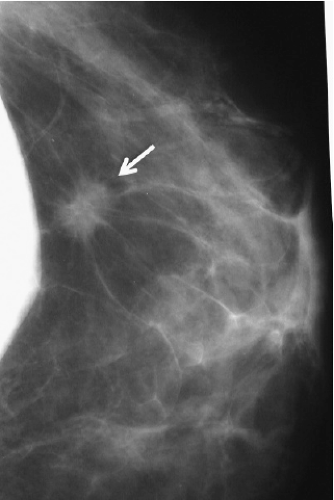

Our study revealed that in most patients there is a decrease in measurable breast tissue on postaugmentation films. The most important factor is capsular contracture: Little or no contracture (Baker 1 or 2) resulted in a 30% reduction in the area visualized, while moderate or severe contracture (Baker 3 or 4) resulted in a 50% reduction (Fig. 15-8). In patients who had serial mammography in the face of worsening contracture, there was progressive reduction in the amount of tissue visualized (Fig. 15-9). Implant position (submammary vs. submuscular) also proved important; on average, patients with submammary implants had a 37% reduction in area visualized, while patients with submuscular implants had only a 17% reduction.

In order to facilitate mammography in augmented women, Eklund et al. (35) developed the displacement or “push-back” technique (Fig. 15-10A,B), by which the implant is displaced posteriorly to allow a greater proportion of breast tissue to be captured on the mammogram. Using standard compression mammography, Eklund et al. determined that up to 97% of the breast tissue could be obscured by the implant, greatly increasing the likelihood of missing a significant lesion. The displacement technique led to an improvement in 99% of cases. Part of this improvement is likely attributable to the fact that implant displacement results in a compression advantage of up to 5 cm, leading to improved image quality and greater sensitivity. Subsequent studies confirmed the results of Eklund et al. in obtaining better visualization of breast tissue using implant displacement (36,37). Our study (38) also confirmed that slightly more tissue is visualized with displacement (average reduction of 25%) than with standard compression mammography (average decrease of 30%); however, with either technique there is a substantial reduction in area visualized compared to preaugmentation mammograms (Fig. 15-11).

While no one refutes that the shadow cast by an implant interferes with visualization of breast tissue, there has been debate about whether this translates into diminished mammographic sensitivity. It has been

established that mammography in nonaugmented women is highly sensitive. In nonaugmented women with palpable tumors, the mammogram is positive in >90% and the false-negative rate is <10%. There are several published reports suggesting that the false-negative rate in augmented patients is considerably higher (37,39,40). We recently reviewed the mammograms of all patients with palpable tumors treated over a 23-year period (41). Mammograms among 1,741 nonaugmented women failed to visualize the tumor in 153 (false-negative rate of 8.8%). The mammograms of 87 augmented patients failed to reveal the lesion in 36 cases (false-negative rate of 41.4%). This difference is highly significant (p < 0.0001) (Table 15-2) and suggests that implants dramatically reduce the sensitivity of mammography.